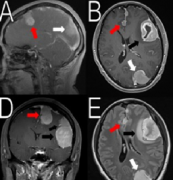

蝶骨嵴脑膜瘤严重吗?内镜下经蝶窦入路切除蝶骨嵴脑膜瘤案例一则

蝶骨嵴脑膜瘤严重吗?下文报告了一例患者,其中蝶窦蝶骨嵴脑膜瘤是通过分期手术切除的,包括颅内部分的开颅手术和蝶窦颅外部分经蝶和经蝶入路的内窥镜鼻内切除术。接下来,打开左侧鼻...